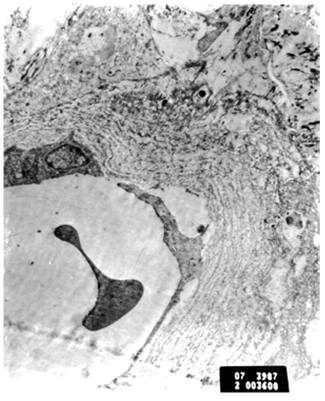

Blood vessels: Small blood vessels showed marked thinning of the endothelial lining cells. Some endothelial cells were degenerated and a few were apoptotic (Figure 4). Endothelial cells showed increased microfilaments especially in the lateral zones with foci of detachment from the underlying basement membrane. Multi layering of the pericapillary basement membrane was also noted with focal irregularity. Larger blood vessels showed large plump endothelial cells alternating with attenuated ones. There was also widening of the intercellular junctions between the endothelial cells (Figure 5). Both the plump endothelial cells and especially the attenuated ones were widely separated and detached from the underlying multilayered basement membrane. The latter showed foci of disruption and loss. Interstitial hemorrhage and collagen deposition were also noted (Figure 6).

Figure 4 Apoptotic change in endothelial cells and marked collagen deposition in interstitial tissue. [EM x7200].

Figure 5 Magnified blood vessel showing part of endothelial cell with actin filament and multilayered basement membrane [EM x12000].

Figure 6 Blood vessels showing marked thinning of endothelial cells and detachment from basement membrane. Multilayered basement membrane with disruption of the layers [EMx9200].